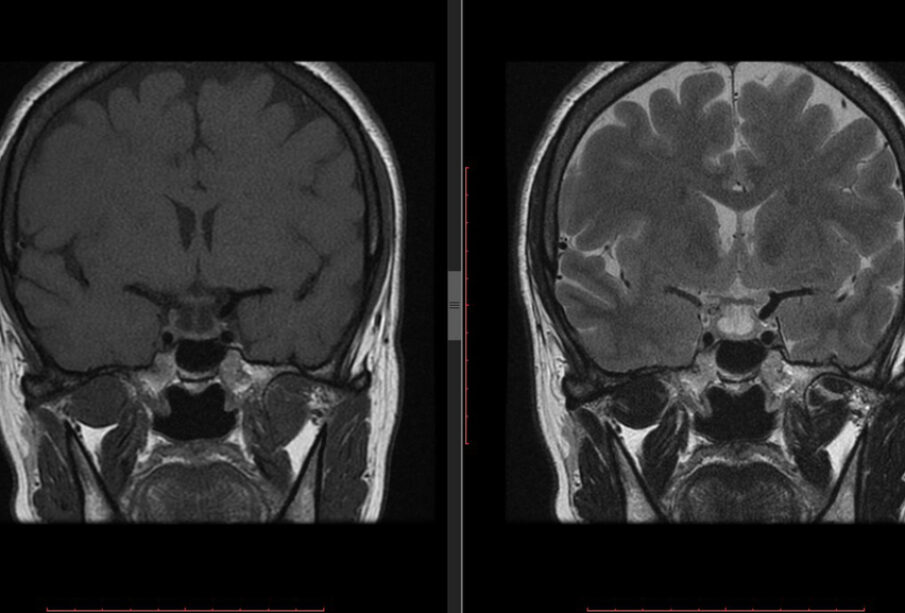

Lakunarinis insultas įvyksta tada, kai užsikemša smulki atšaka didesnio smegenų kraujagyslės. Dėl to šie insultai dažniausiai pažeidžia giliau esančias smegenų sritis, kur gausu mažų kraujagyslių šakų.

Kiekviena smegenų sritis atsakinga už tam tikras funkcijas, todėl lakunarinio insulto požymiai priklauso nuo to, kuri dalis buvo pakenkta. Paprastai jie patenka į vieną iš penkių pagrindinių tipų.